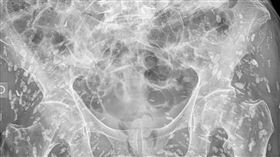

阿嬤X光片驚見下半身布滿白點 醫生嚇傻

泰國一名曾任職診所X光助理的網友分享了一段令人難忘的...

婦照X光「體內佈滿白點」 恐怖真相曝光

一名曾擔任診所X光助理的泰國網友分享,多年前有一位上...